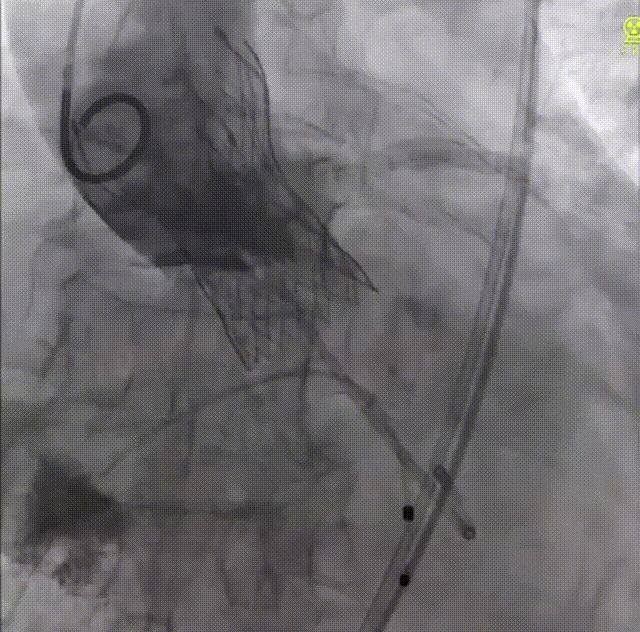

术前,宋光远教授团队对患者基本情况进行反复研究,确定患者不适合外科开胸手术,遂决定选择微创的经导管二尖瓣夹合术。术中经股静脉入路,在超声介导下成功完成房间隔穿刺并建立导丝路径。随后,宋光远教授通过信息采集机器人的高清摄像设备清楚展示了MitraClip系统手术器械的准备过程,对Clip、SGC、CDS及固定装置进行排气及体外调试,以及后续的手术过程。由于患者左前降支存在严重狭窄且合并房颤,如何保障患者围手术期血流动力学稳定是完成手术的重要难题。在食道超声及X线引导下,应用两个MitraClip的二尖瓣夹反复调整夹取位置,最终成功捕获并夹合返流严重部位,使二尖瓣在收缩期由大的单孔变成小的双孔,从而减少二尖瓣返流。二尖瓣夹释放后,超声显示返流几近消失,患者各项生理指标正常。

术前彩超结果

术后彩超提示返流几乎消失